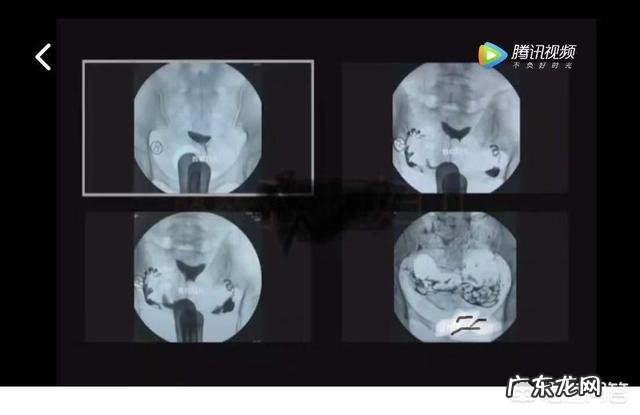

输卵管远端病变分为闭锁性、非闭锁性两种类型 。闭锁性病变即为输卵管积水,在造影片上表现为远端闭锁、壶腹部膨大、似腊肠样或囊袋样 。非闭锁性远端病变则为输卵管远端粘连或伞端部分闭锁 。

输卵管积水也分为可修复性和不能修复性,两者的区别在于显影边缘的清晰度、是否有毛玻璃影

文章插图